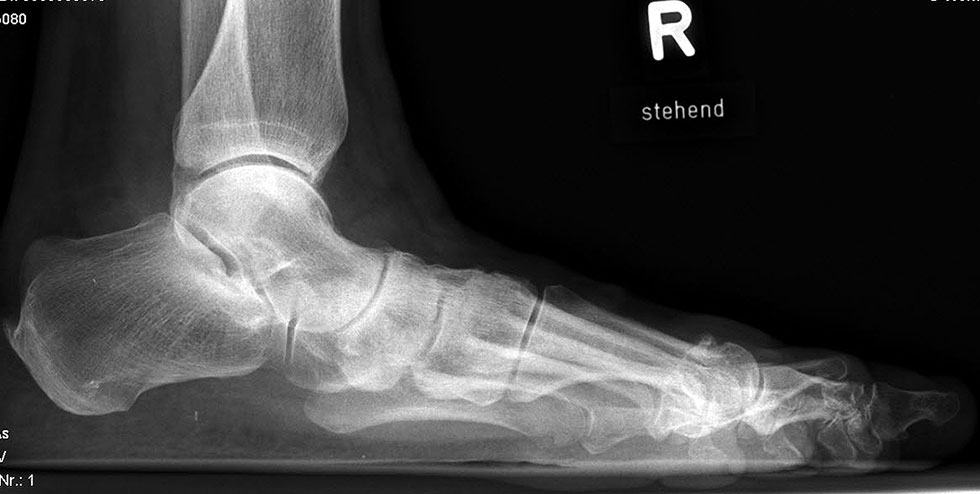

Stehende Aufnahmen des Fußes dorsoplantar (dp) und seitlich sowie des OSG anteroposterior (ap) sind die Grundlage der konventionellen Röntgendiagnostik (Abb. 5). Ergänzend werden gelegentlich die Rückfuβ-Alignement Aufnahme nach Saltzman 19 und Vergleichsaufnahmen der Gegenseite durchgeführt.

Der Talo-Metatarsale I Winkel bzw. die laterale talonaviculare Subluxation auf der stehenden dorsoplantaren Aufnahme des Fuβes dokumentieren das Ausmaβ des Vorfuβ abductus (Abb. 6 a,b). Ein dp Talo-Metatarsale I Winkel von > 10° (nach medial konvex) ist als pathologisch anzusehen. Mit der Bestimmung der talocalcanearen Divergenz (Abb. 6 c) erhält man ein Eindruck über das Ausmaβ des Rückfuβ valgus; eine leichte Divergenz bis ca. 12° gilt als physiologisch 20.

Auf der seitlichen, stehenden Aufnahme des Fußes wird ebenfalls der laterale Talo-Metatarsale I Winkel (Abb. 6 d) gemessen und so das kollabierte mediale Längsgewölbe dokumentiert. Auch hier gilt ein Talo-Metatarsale I Winkel von > 5° (nach plantar konvex) als pathologisch 21. Der Kollaps findet dabei meist im Talonaviculargelenk, seltener in der Naviculocuneiform-Gelenkreihe statt. Instabilität und Arthrose im 1. TMT sollten ausgeschlossen oder bei der Operationsplanung mit einbezogen werden. Weitere wichtige radiologische Messungen zur Beurteilung der Planovalgus-Statik und Progression der Deformität sind der laterale talo-calcaneare Winkel (Abb. 6 e) und der Abstand des Os cuneiforme-Unterrandes zum Untergrund (Abb. 6 f, Cuneiform height, 22. Eine anteriore Translation des Talus auf dem Kalkaneus findet man sowohl auf der ap, als auch auf der seitlichen Aufnahme des Fuβes mit Aufhebung der Cima-Linie.

Die stehende OSG ap -Aufnahme kann zunächst das fibulocalcaneare Impingement und im Endstadium laterale OSG Arthrose oder Valgus-Tilt des Talus zeigen.